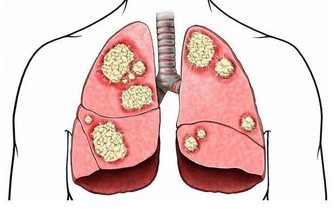

肝作為人體最為重要的代謝器官,如果肝不好的人,人的健康肯定是會受到影響的,而夜裡頻繁醒來,很可能就是肝出問題了。

肝臟是我們身體內的重要器官,也是較為脆弱且容易患病的一個器官。不僅病毒感染可以導致肝病,飲食不當乃至休息不當都會導致肝病的發生。所以,日常生活中除了充足的睡眠之外,飲食對於肝臟的保護就顯得格外重要。那麼如果你的身體產生這些症狀,該好好保護你的肝髒了!